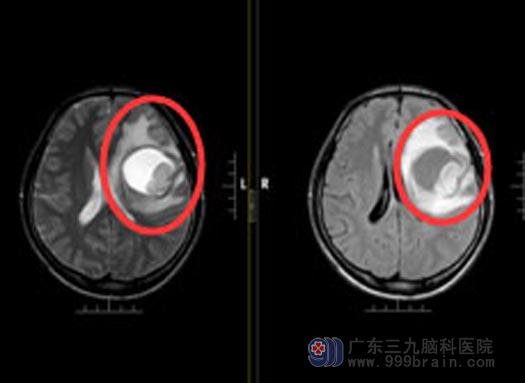

解除家人的顾虑后,由鲁明主任主刀在唤醒麻醉下行“左侧额叶囊实性占位病变切除+硬膜修补+颅骨成型术”。准确定位肿瘤的位置,顺利开颅,充分的准备后,小莫被医生唤醒,在电生理的监测下和小莫聊天,让他完成指定的动作,手术中避开运动、语言等功能区,将肿瘤完整解除,手术很顺利。

手术前

手术后